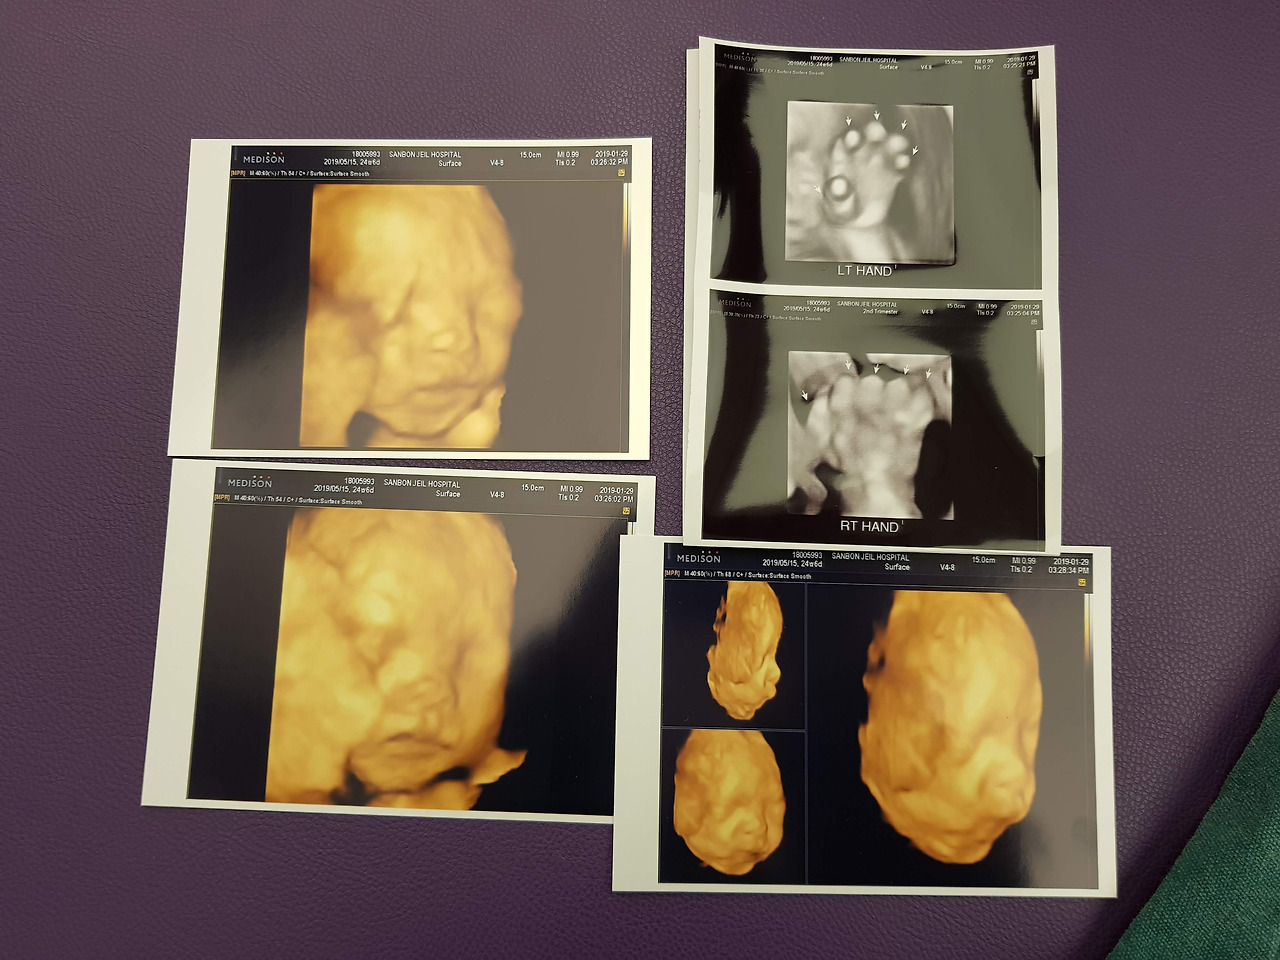

20190129_163442.jpg 짠짠이 25주 차

25주.

입체 초음파 촬영. 추가 비용이 좀 들지만 안 하기엔 영 아쉬운 것 같다. 촬영 당시 태아 자세가 중요한데 얼굴을 손으로 가리거나 하면 선명한 모습을 볼 수 없다고. 엄마가 단 것을 먹으면 태아 움직임이 활발해진다고 하여 매번 초음파 찍기 전마다 초코우유 섭취는 필수! 짠짠이는 오른손만 얼굴에 대고 있는 정도로 적당히 협조해주었다. 코랑 입술 형태만 어느 정도 보이고 전반적으로 영 애매하게 찍혔다 싶었는데 나중에 짠짠이가 실제로 나온 모습과 놀랄 만큼 똑같았다. 다시 한번 공돌이 찬양해!